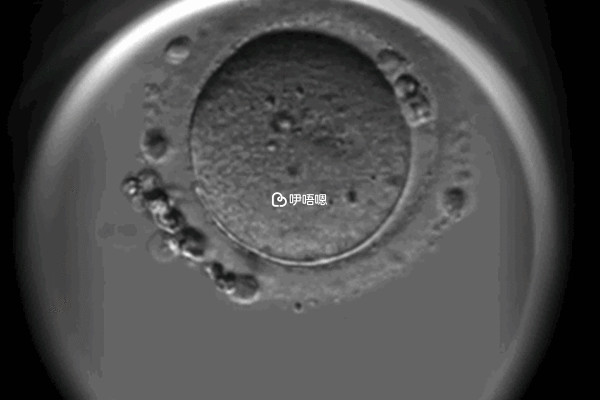

卵子冷凍是指對卵母細胞進行冷凍和超低溫儲存,以治療不孕症以及儲存女性生育力為目的的醫療技術,可以阻止卵子衰老,當女性有生育意願時,可以將冷凍的卵子取出,進行解凍,以下則是女人冷凍卵子最佳年對照表: